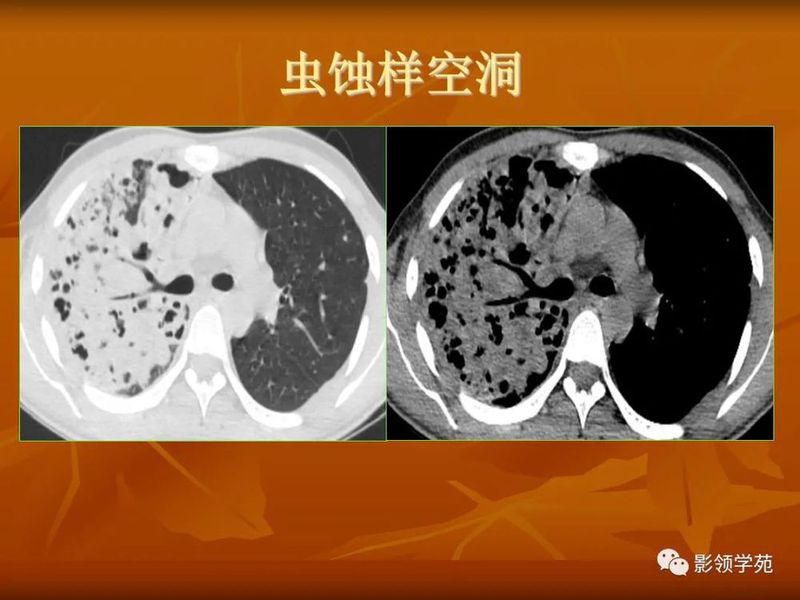

(1)较大含空洞性肿块,洞壁较厚,大于15mm,空洞外壁有分叶、毛刺,洞壁凹凸不平有壁结节,增强可见不规则强化,周围未见明显卫星病灶时,首先考虑周围型肺癌;癌性空洞洞壁一般肺门侧较厚,空洞多偏于外侧,伴有同侧淋巴结肿大更支持肺癌诊断。

(2)空洞病变发生于双肺上叶尖后段、下叶背段,病变周围可见点状、结节状及片状卫星病灶,洞壁组织无明显强化或有包膜线样强化时,考虑结核;结核球的空洞多位于病变的肺门侧,与引流支气管相同,洞内壁一般较光滑。

(5)肺内多发结节,由肉芽肿和炎症构成,较大结节发生空洞,多数结节边缘见有血管进入,则要考虑到肺韦格氏肉芽肿可能。